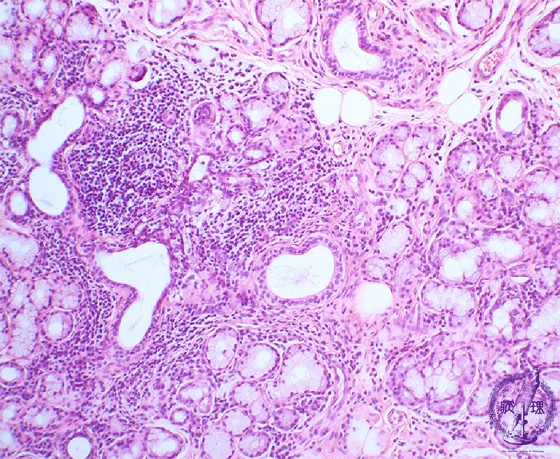

- 7.Oral, Salivary gland

- ★(4)Sjögren's syndrome

Microscopic finding (HE stain, low-power view):Labial gland biopsy. Lymphocytes (*), predominantly composed of T cells, focally infiltrate around interlobular ducts of minor salivary glands. In the background, there is acinar atrophy and destruction with (associated?) ductal dilatation.